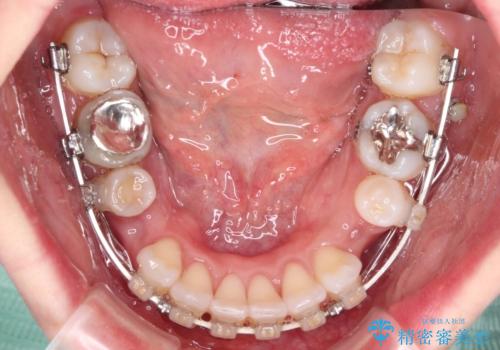

- 口元の閉じにくさと、奥歯の咬み合わせを気にして来院された患者様です。

左下の大臼歯2本が顕著に舌側に傾斜しているため、まずは奥歯の咬み合わせを改善をし、その後上下左右の第1小臼歯4本を抜歯することで口元を引っ込めながら整えることとしました。

奥歯の咬み合わせ改善には1年ほどの期間と処置中の噛みにくさを強いることとなりましたが、抜歯後はスムーズに治療を完了させることができました。